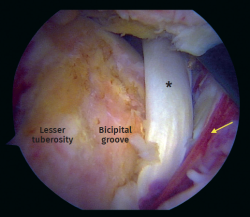

Figure 2. Arthroscopic view from anterolateral portal on a right shoulder in beach chair positioning. Chronic biceps tendon rupture. Arrow: Full-thickness and retraction of the subscapularis tendon

Figure 5. Arthroscopic view. Full-thickness subscapularis tear with medial instability of the long head of the biceps tendon. Asterisk: biceps tendon. Arrow: torn subscapularis tendon.